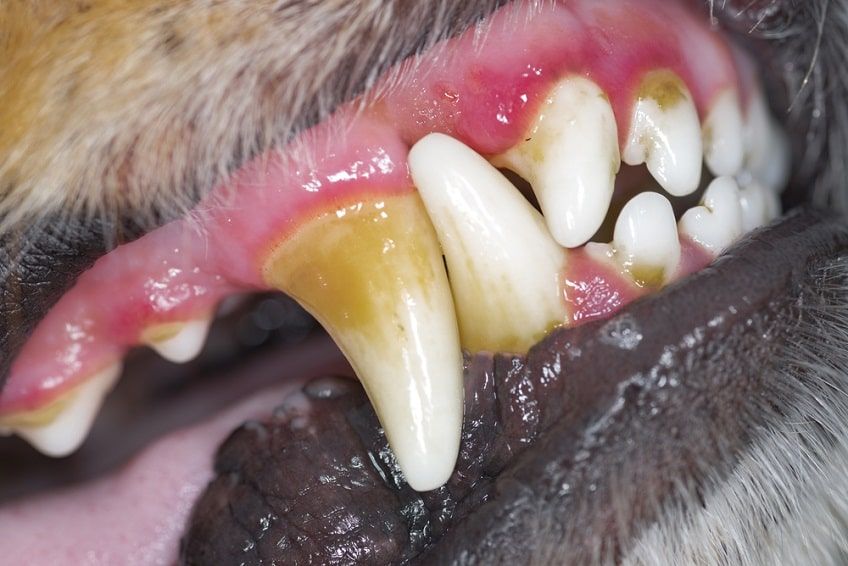

Zdrowe dziąsła u psa mają charakterystyczny różowy kolor – ciemniejszy lub jaśniejszy, w zależności od indywidualnych cech zwierzaka. Często na psich dziąsłach znajdują się czarne plamy, które wynikają z naturalnej pigmentacji i nie są powodem do obaw. Jednak u większości czworonogów bez trudu znajdziemy niewybarwione fragmenty. Psie dziąsła powinny być mokre i śliskie, a po naciśnięciu na nie palcem ich kolor powinien bardzo szybko wracać do pierwotnego. Jeśli dziąsła naszego psa mają inny kolor, są suche i lepkie, może to świadczyć o chorobie!

• Ciemnoczerwone dziąsła u psa to objaw między innymi przegrzania i udaru cieplnego. Mogą także świadczyć o przeróżnych stanach zapalnych, chorobach i infekcjach w obrębie pyska, zębów i dziąseł.

Choroby dziąseł u psa – przyczyny

Dziąsła psa narażone są na kontakt z wieloma patogenami. Część z nich nie przeżywa w kontakcie ze śliną psa, jednak niektóre doskonale rozwijają się w ciepłym, wilgotnym środowisku. Organizm psa dość dobrze radzi sobie z mikroorganizmami zamieszkującymi w jamie ustnej. Jednak gdy dojdzie do uszkodzenia naturalnej bariery obronnej, patogeny przenikające do wnętrza uszkodzonych tkanek wywoływać będą stany zapalne wewnątrz jamy ustnej psa. Może doprowadzić do rozwoju zapalenia dziąseł u psa. Główną przyczyną nadmiernego namnażania się bakterii w jamie ustnej psa jest kamień nazębny. Pojawieniu się zapalenia dziąseł u psa sprzyjają także:

Objawy zapalenia dziąseł u psa

W początkowym stadium zapalenie dziąseł u psa może nie powodować żadnych wyraźnych objawów. Sprawia to, że opiekunowie zgłaszają się do lekarza weterynarii zazwyczaj dopiero, gdy zauważą:

• nieprzyjemny zapach z jamy ustnej pupila,

• krwawienie dziąseł,

• nadmierne ślinienie się,

• niechęć do jedzenia (szczególnie twardych gryzaków i suchej karmy),

• objawy bólu podczas dotykania pyska psa,

• opuchnięte dziąsła u psa,

• kamień na powierzchni zębów.

Zaawansowane stany zapalne objawiać się mogą również poprzez tworzenie się owrzodzeń na błonie śluzowej, wysięk ropy z jamy ustnej, poluzowanie się i utratę zębów. Mogą stać się także przyczyną złamania kości żuchwy czy utworzenia się przetoki ustno-nosowej.